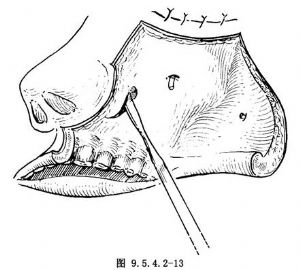

(4)去除上頜骨的前、後、內、外骨壁,包括中、下鼻甲,僅保留其眶底及上牙槽骨。去除後壁的骨質不要太向上靠近眶底,以免損傷眶尖部組織。但內壁必須將其最靠後側部分--齶骨垂直板去除,充分暴露,以蝶齶切跡(incisura sphenopalatina)爲其下緣的蝶齶孔,並使鼻腔、上頜竇腔、鼻咽腔、翼齶窩及顳下窩融爲一個相連的腔,便於摘除啞鈴狀腫瘤的兩端及其中央莖部(圖9.5.4.2-14)。

(5)將翼齶窩及顳下窩的腫瘤分離並推向上頜竇腔內,在此過程中,可將顯露的頜內動脈結紮切斷,在蝶齶孔處將腫瘤莖部鬆解後,即可連同鼻咽腔的腫瘤一起摘除。